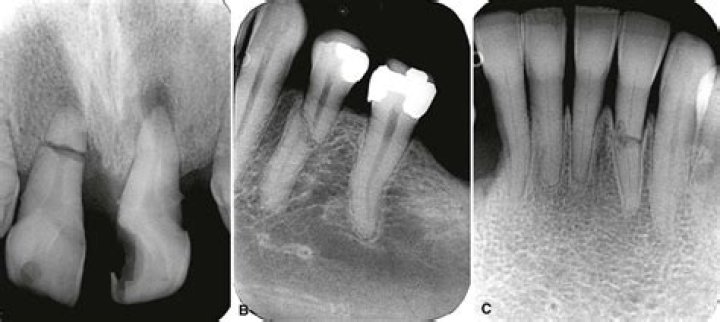

Fractured cusp.

This occurs when a piece of the chewing surface of a tooth breaks. A fractured cusp is most common around a dental filling.

How do you treat a vertical root fracture?

In a literature review, the treatment of complete vertical root fracture is the extraction of the tooth followed by dental prosthesis or implant or joining the separated fragments by different types of bonding system, laser or bioceramic cements, and reimplantation with a good success rate.

How common are vertical root fractures?

Vertical root fractures represent between 2 and 5 percent of crown/root fractures. The greatest incidence occurs in endodontically treated teeth, and in patients older than 40 years of age.